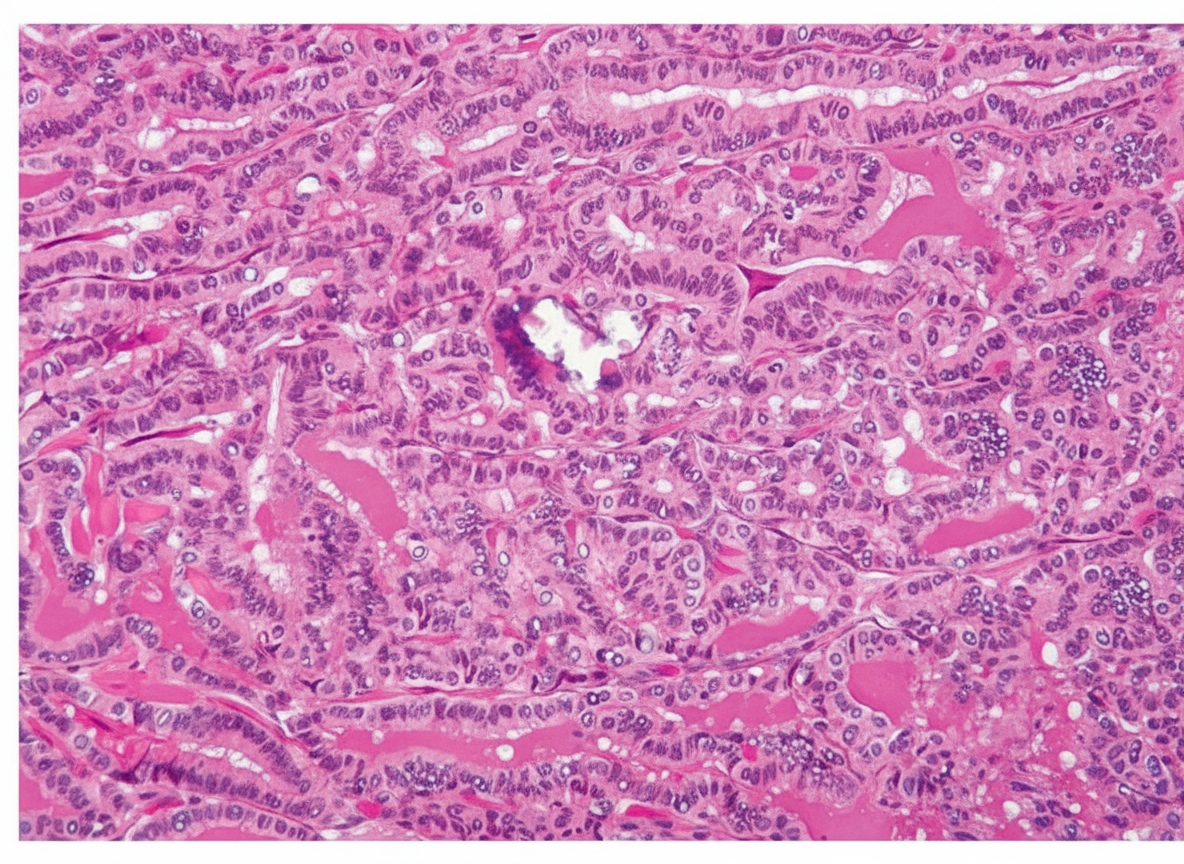

A tumor similar to that shown in the illustration is observed in a biopsy specimen from the thyroid of a 50-year-old woman. An adjacent lymph node is also involved. Which of the following descriptions of this tumor is most appropriate?

Explanation: ***Slow-growing lesion with relatively good prognosis*** - The histological features described suggest **papillary thyroid carcinoma**, which has an excellent prognosis with **10-year survival rates >95%**. - Despite **lymph node involvement**, papillary carcinoma grows slowly and responds well to **surgical resection** and **radioiodine therapy**. *Functional tumor resulting in thyrotoxicosis* - **Papillary thyroid carcinoma** is typically **non-functional** and does not produce excess thyroid hormones. - Functional tumors causing thyrotoxicosis are usually **toxic adenomas** or **toxic multinodular goiter**, not malignant lesions. *Origin from C cells* - **C cells** (parafollicular cells) give rise to **medullary thyroid carcinoma**, not papillary carcinoma. - Papillary carcinoma originates from **follicular epithelial cells** and shows characteristic **papillary architecture** with **Orphan Annie eye nuclei**. *Calcitonin-producing tumor* - **Calcitonin** is produced by **medullary thyroid carcinoma** arising from C cells, not papillary carcinoma. - Papillary carcinoma produces **thyroglobulin** as a tumor marker, which is used for monitoring recurrence after treatment.